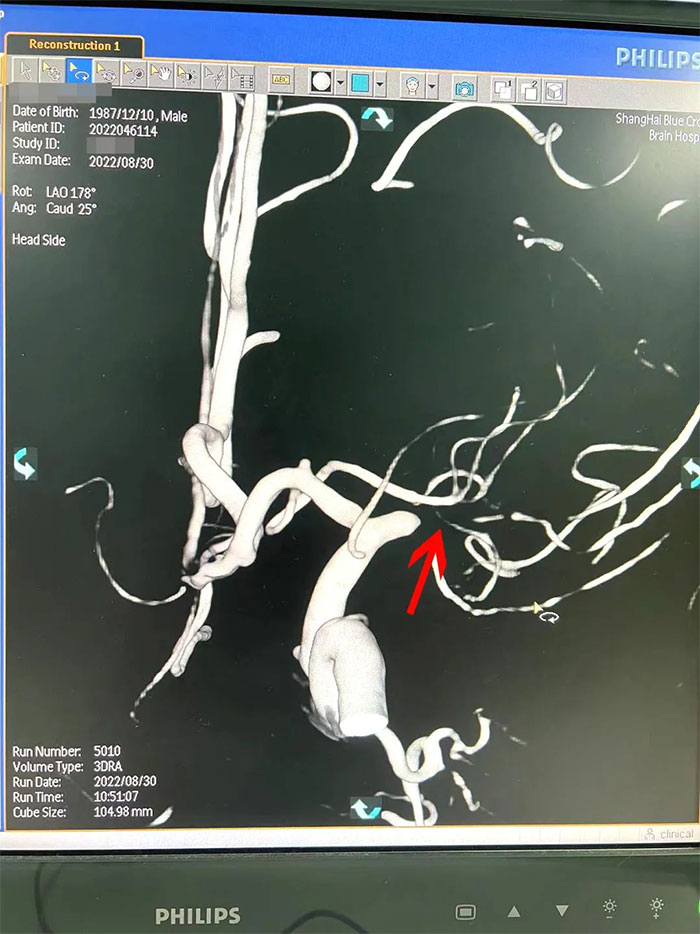

在檢查中發(fā)現(xiàn),周先生右側(cè)大腦中動脈M1段閉塞,可見煙霧狀異常血管網(wǎng)生成;左側(cè)大腦中動脈M1段重度狹窄(約70%)。符合煙霧病的典型影像學(xué)特征。

▲右側(cè)大腦中動脈M1段閉塞,左側(cè)重度狹窄

煙霧病又名Moyamoya病,腦底異常血管網(wǎng),是一組以Willis環(huán)雙側(cè)主要分支血管(頸內(nèi)動脈虹吸段及大腦前、中動脈,有時也包括大腦后動脈)起始部慢性進行性狹窄或閉塞,繼發(fā)出現(xiàn)側(cè)支異常的小血管網(wǎng)為特點的腦血管病。因腦血管造影時,呈現(xiàn)許多密集成堆的小血管影,似吸煙時吐出的煙霧而得名。